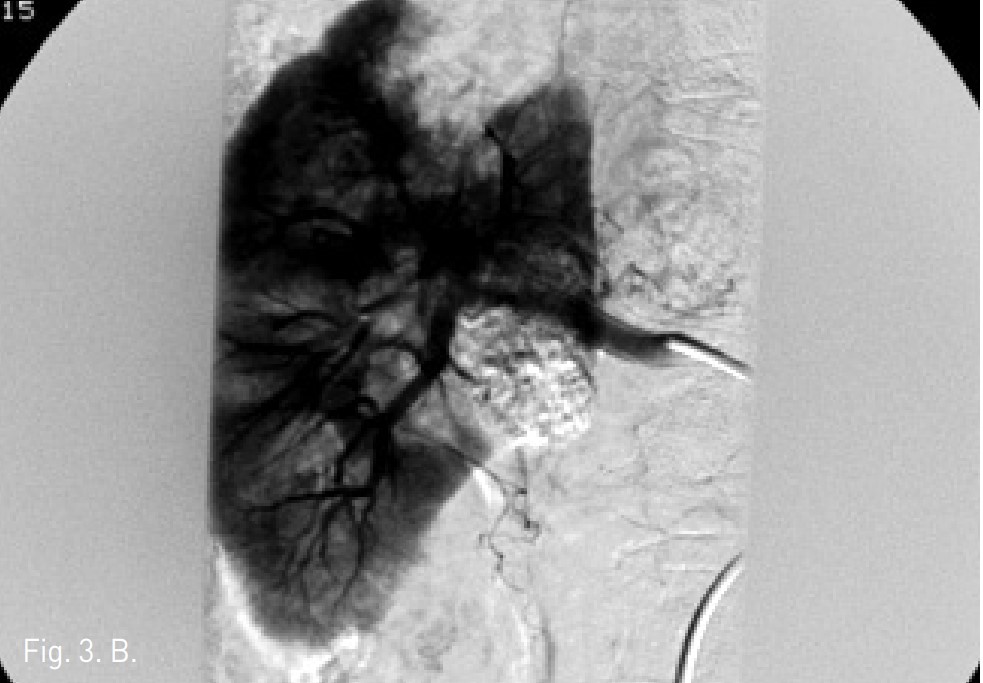

Fig. 3. Renal angiography by supers election for middle segmental artery showed 2cm sized hypervascular RCC (A). After embolization by injection of mixture with ethanol 5mL and lipiodol 2mL, RCC was not detected on post-angiography (B).

Fig. 3. B

5 Fr pigtail catheter를 right femoral artery를 통하여 suprarenal aorta에 삽입하고 혈관조영술을 시행하였음. 복부 CT에 대응되는 right middle segmental renal artery에서 supply 되는 약 2cm 크기의 과혈관성 종괴가 관찰됨(Fig. 3A). 5 Fr Yashiro catheter를 middle segmental renal artery에 삽입하고, 시행한 혈관조영술에서 종괴를 확인하고, 3 Fr microcatheter를 0.018 inch guide wire를 이용하여 co-axial technique으로 middle segmental artery의 branch를 superselection 한 후 시행한 혈관조영술에서 2개의 abnormal feeding artery를 확인하였음. Ethanol 5mL와 lipiodol 2mL를 혼합한 용액의 2/3를 이용하여 2개의 small vessel를 embolization하였음. 혈관조영술에서 right middle segmental artery의 종괴에 lipiodol

uptake가 보이고, emolization된 상태임 (Fig. 3B). 우측 신종양은 색전술 후 초음파에서 뚜렷이 증가된 에코음영의 종괴로 보였으며 (Fig. 4), Radionics 3cm Cool-tip electrode를 이용하여 고주파열치료를 12분간 시행하였음.